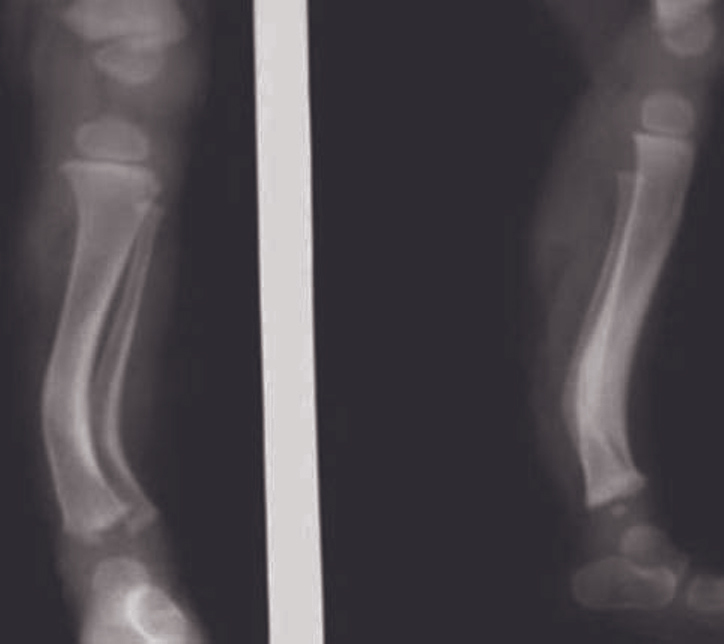

Radiographs of left leg were taken in the AP and lateral projection (foot was manually plantar flexed). It revealed bowing of tibia and fibula with the apex of curve directed posteromedially. Cortical thickening with narrowing of the medullary cavity on the concave side of the curve was evident (Fig. 1). Based on the clinicoradiologic findings, the diagnosis of prenatal bowing of tibia and fibula was made.

Fig. 1.

An AP and lateral radiograph of left leg (with manual plantar flexion of foot) at 5-days show posteromedial bowing of tibia and fibula with thickening of cortex on inner side of curve with narrowing of medullary cavity